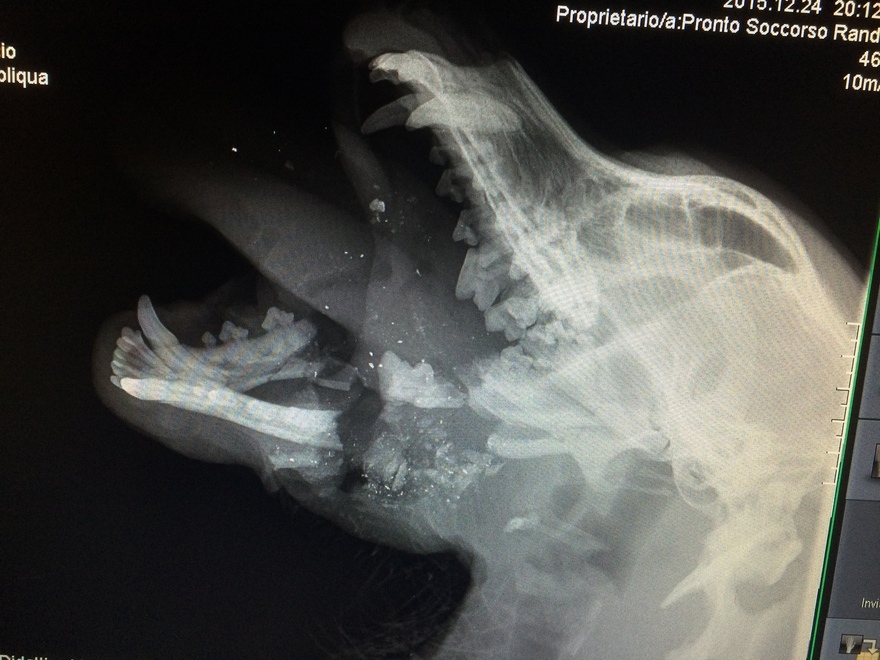

SASSARI – Un cane di razza setter è stato colpito da un colpo di fucile durante una battuta di caccia a Ploaghe, in provincia di Sassari. Il suo nome è Santiago e, per tentare di salvargli la vita, è stato ricoverato nel reparto di terapia intensiva dopo che era stato trovato agonizzante, senza la mandibola e con la lingua completamente bruciata. Dopo ben quattro ore di intervento, condotto dalla clinica veterinara dell’Università di Sassari il cane è riuscito a salvarsi e non è più in pericolo di vita e i medici credono si riprenderà.

L’ipotesi iniziale era che Santiago, un cane ben conosciuto a Ploaghe, fosse stato colpito da un petardo. Poi, dopo un attento esame da parte dei veterinari, è emerso chiaramente che la devastazione del suo volto era stata provocata da un colpo sparato da un fucile da caccia sparato, presumibilmente, da lunga distanza.